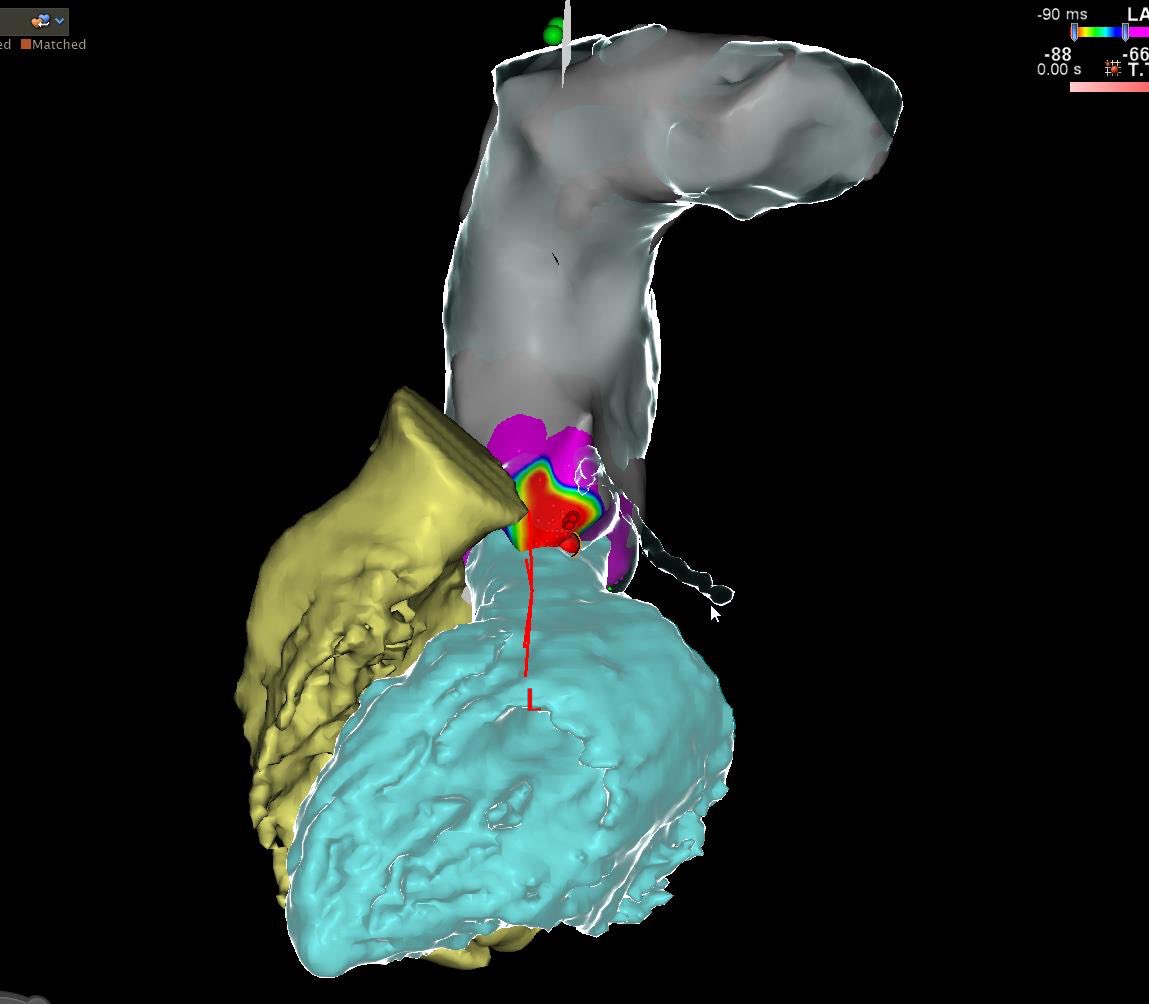

High MDI had me concerned about Epi or intramural origin. Early in AIV on top of LCX, matched opposite location in LCC and was 20-25ms earlier, success with 35w. #ablatePVC